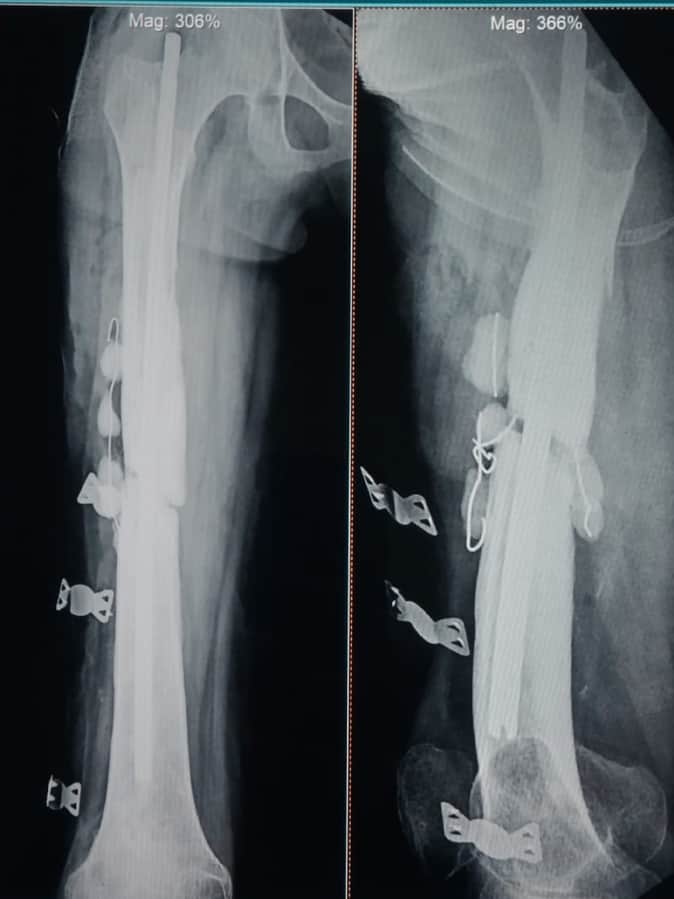

हड्डी में स्थापित एंटीबायोटिक इम्प्रेग्नेंटेड नेलिंग।

- फोटो : हड्डी में स्थापित एंटीबायोटिक इम्प्रेग्नेंटेड नेलिंग।

अमेठी सिटी। तिलोई स्थित मेडिकल कॉलेज के अस्थि रोग विभाग के चिकित्सकों की टीम ने मरीज की संक्रमित जांघ की हड्डी की जटिल सर्जरी की है। ऑपरेशन के बाद मरीज के पैर की हड्डी में एंटीबायोटिक इम्प्रेग्नेंटेड नेलिंग (औषधि मिश्रित रॉड) स्थापित की गई है। चिकित्सकों के मुताबिक, मरीज का स्वास्थ्य लगातार सुधर रहा है।

तिलोई में भर्ती मरीज गीता की दो वर्ष पूर्व जांघ की हड्डी टूट गई थी। ऑपरेशन के समय हड्डी जोड़ने के लिए धातु की रॉड लगाई गई थी, लेकिन ऑपरेशन के बाद हड्डी में संक्रमण बढ़ता गया। रॉड हटाने के बाद भी समस्या बनी रही। तिलोई मेडिकल कॉलेज में जब मरीज की जांच हुई तो पता चला कि हड्डी में ज्यादा दिन से संक्रमण होने के कारण सड़न फैल गई थी। विभागाध्यक्ष डॉ. प्रेमी विजय कुमार ने टीम के साथ हाल ही में गीता के पैर का ऑपरेशन किया और संक्रमित हड्डी के खराब हिस्से को हटा दिया।इसके बाद हड्डी में एंटीबायोटिक इम्प्रेग्नेंटेड नेलिंग स्थापित की गई और संक्रमण वाले हिस्से में औषधि कण डाले गए।

विभागाध्यक्ष ने बताया कि यह तकनीक हड्डी के भीतर निरंतर औषधि छोड़ती है, जिससे जीवाणु नष्ट होते रहते हैं और संक्रमण थमता जाता है। सामान्य स्थिति में यह रॉड लगभग छह माह तक रहती है। मवाद बंद होने और हड्डी जुड़ने पर इसे सुरक्षित निकाल दिया जाता है। संक्रमण समाप्त होने पर औषधि कण भी हटा दिए जाते हैं। सर्जरी टीम में विभागाध्यक्ष के साथ सहयोगी चिकित्सक डॉ. बिरेन, डॉ. अरविंद, डॉ. जितेंद्र, ओटी तकनीशियन शिव, आदित्य, शैलेश व नर्स संध्या शामिल रही।